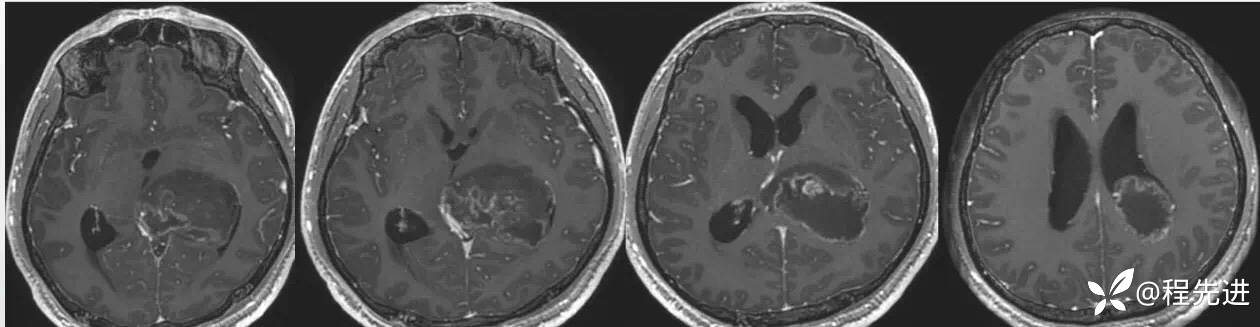

FLAIR冠状位:

T1增强: